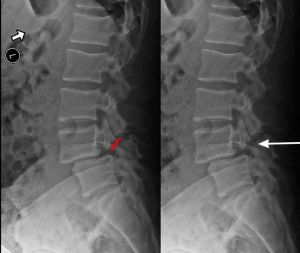

X-RAY SHOWING A PARS FRACTURE DEFECT

THE WHITE OUTLINE SHOWS THE SLIPPAGE.

Spondylolisthesis is most commonly found in the lumbar spine as these levels bear the most weight. To assess instability, we take x-rays of a patient bending forward (flexion) and bending backwards (extension). Normally there would be no motion. The more motion seen between flexion and extension x-rays across an injured level, the greater the patient’s symptoms usually appear.